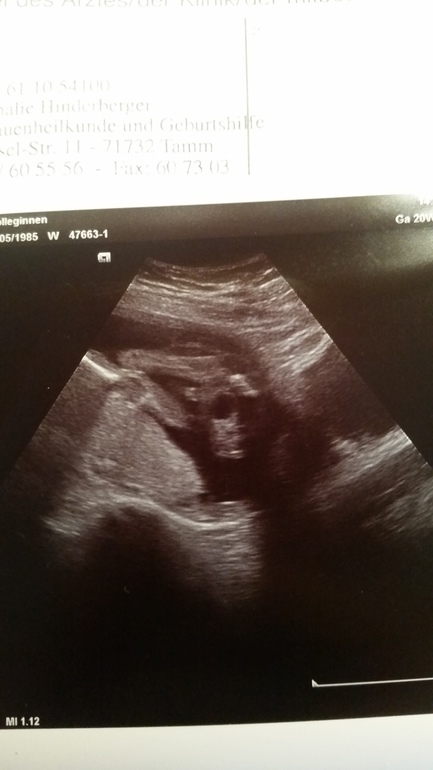

Экваторну вот и у нас наступило 20 недель. И сегодня мы посетили узи, пошла я со своими 3-мя детьми, папа пойти не смог, на работе ;( все соответствует сроку, малявка пинается уже во всю. весит уже 330 гр. и теперь я могу смело перекрасить свой кружочек. У нас будет 3 мальчик. доча растроилась, но я думаю привыкнет, что будет единственной принцесой;) ну и дали фото для папы...